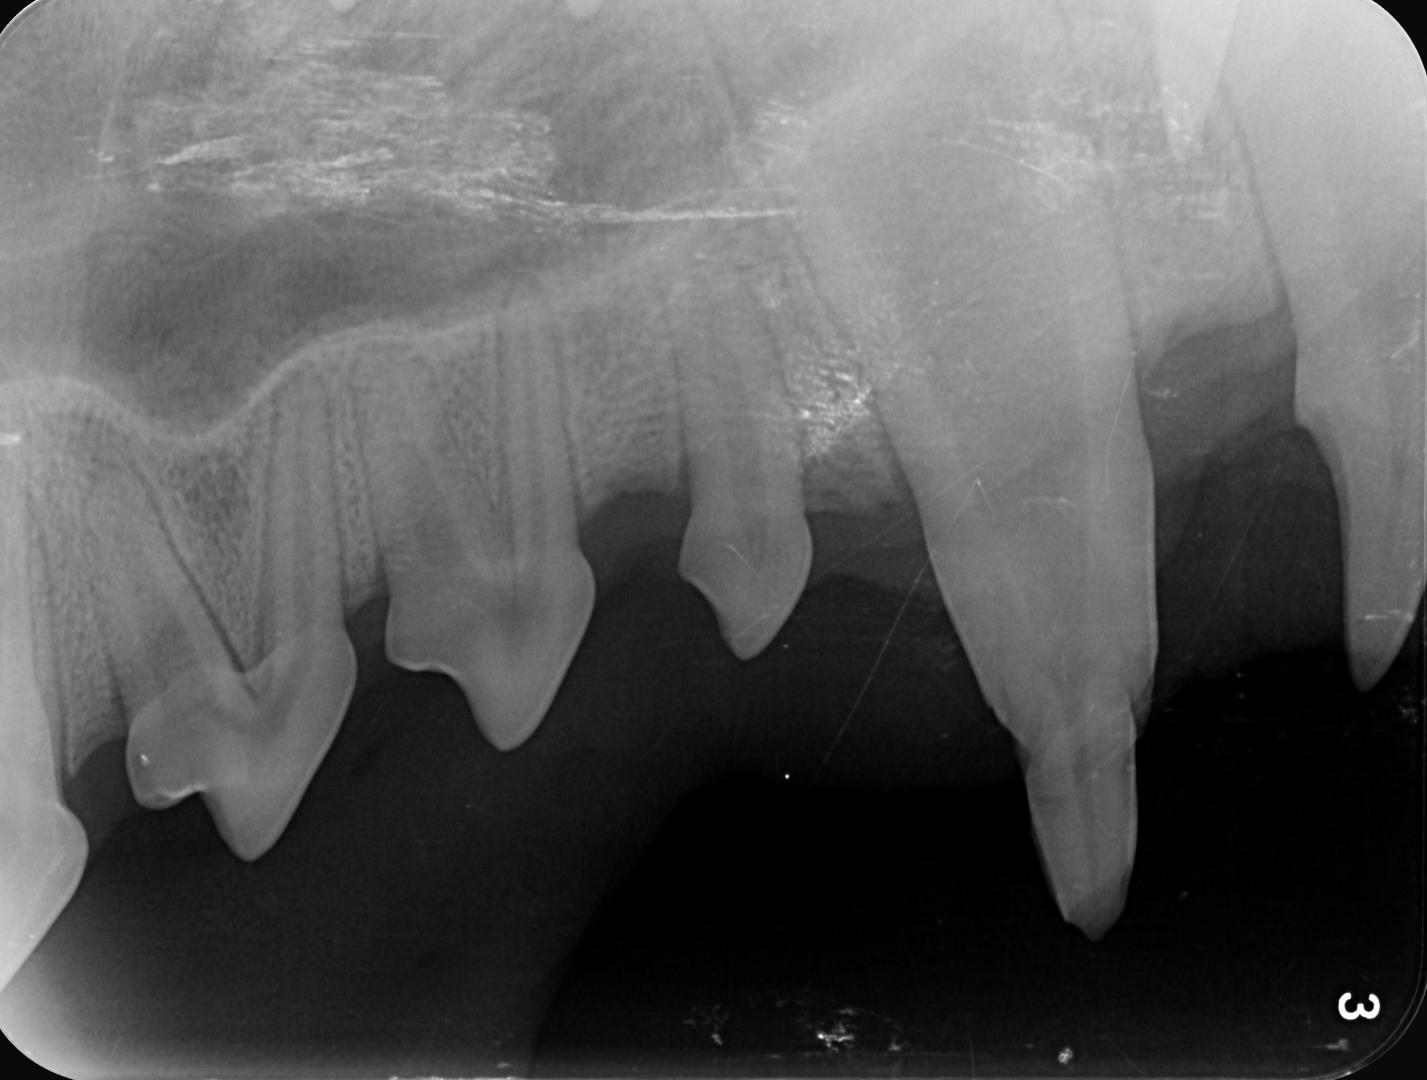

La radiographie est indispensable dans ce cas pour vérifier la meilleure conduite à tenir :

radio croc

Dans le cas d'Alphonse :

- l'apex est fermé (cercle vert) sur les 3 dents concernées ; aucun abcès n'est visible et donc la pulpe ne présente pas de signe de contamination (vérifié également par sondage, le canal n'est pas perméable)

- La couche de dentine semble déjà conséquente et suffisante pour donner une chance à la dent (trait bleu) ;

La décision est donc prise de tenter de la conserver, et de protéger la pulpe en déposant une couche de résine pour combler les surfaces abîmées du croc.